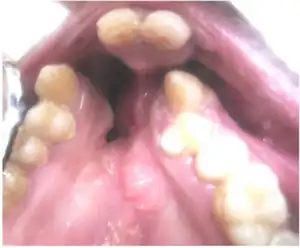

| Image of two bilaterally symmetrical lip pits on the lower lip. | |

There are three types of lip pits, which are classified according to their location: midline upper, comissural, and lower lip. The most common phenotype is two symmetrical lower lip pits flanking both sides of the midline in the bilateral paramedial sinuses. Lower lip pits may also be bilaterally, unilaterally, or medially asymmetrical. The occurrence of a single lip pit is considered incomplete expression, and it typically occurs on the left side of the lower lip. There are also three different shapes for lip pits, the most common being circular or oval; less common forms include slit-like or transverse. The lip pits extend into the orbicularis oris muscle, ending in blind sacs surrounded by mucous glands. In some cases mucous is excreted when the muscles contract.[4]